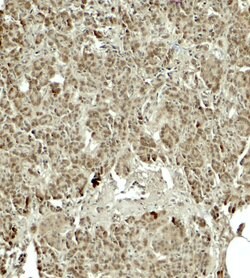

KIRREL2 Polyclonal Antibody for Western Blot, IHC (P), ELISA

| ELISA, Immunohistochemistry (Paraffin), Western Blot | |